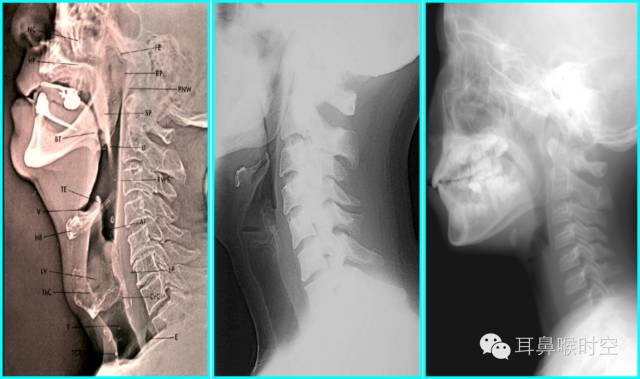

X线摄片Chest radiography

常规:站立后前位

侧位:病变定位

咽部正常X线表现

鼻咽部侧位X片的摄片方法

体位:患儿端坐或站立侧位,下颌略抬高,以减少下颌支与鼻咽腔重叠,眶耳线平行于地面,头颅矢状面与摄片架平行。

中心线:通过外耳孔前下方约2cm处。

注意:嘱患儿闭口用鼻吸气并摄片,防止软腭抬高造成鼻咽腔变窄的假象。